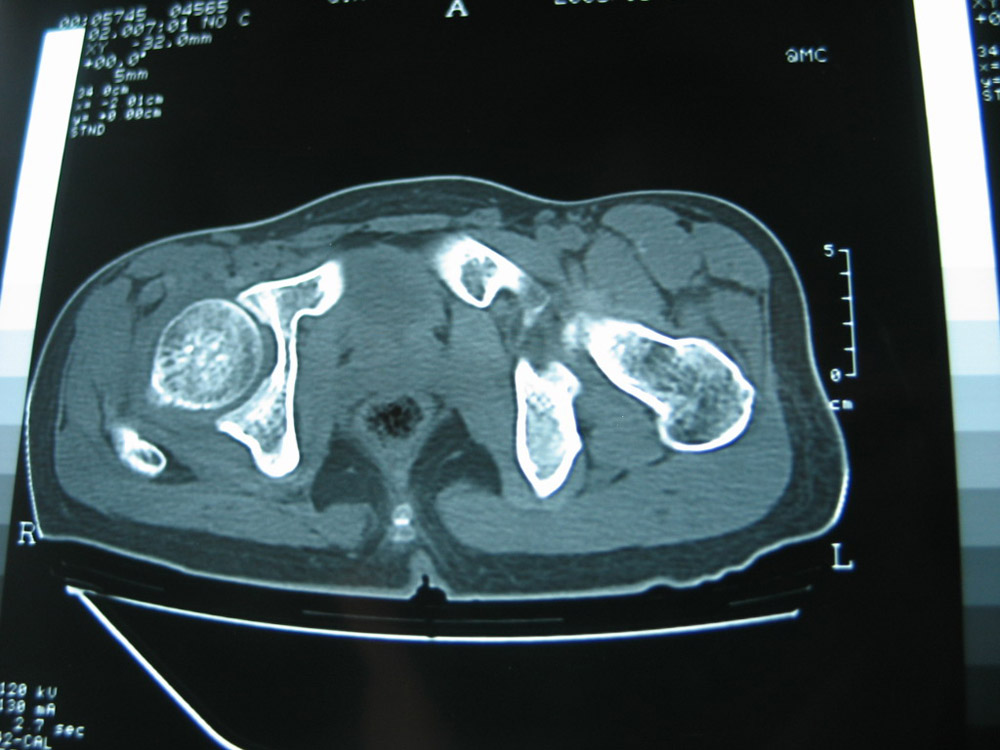

以下是引用卜一在2007-1-25 16:33:00的发言:[br]右侧髋关节股骨头及髋臼骨骨小梁疏松 粗糟,股骨头外形毛糟,软组织似肿胀,间隙略变窄.考虑:1 髋关节结核可能性大.2 缺血性坏死?3 化脓性髋关节炎?

以下是引用hhcckk在2007-1-25 17:18:00的发言:[br][br]支持髋关节结核,[br]依据关节面破坏,有脓肿,脓腔内有钙化,关节周围增生不明显,鉴别[br]1化脓性的病变增生明显,临床上有高热[br]2创伤引起的关节炎,无菌坏死不会引起关节面的破坏,而且不会在这么短的时间内出现[br]